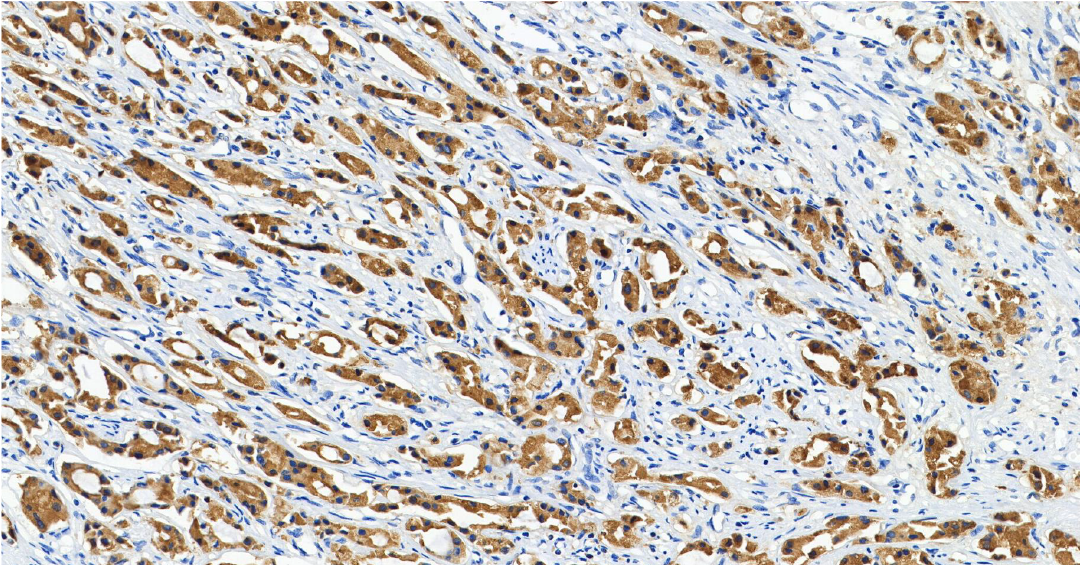

MET

MET ——MET 基因是定位在人类第 7 号染色体上的一个原癌基因,其编码生成的 c-Met 蛋白属于受体酪氨酸激酶家族。

定位: 细胞膜。

功能: MET 是肝细胞生长因子 (HGF) 的受体。正常的 HGF/MET 信号通路精密调控胚胎发育、组织再生和损伤修复过程中的细胞增殖、分化和迁移。

在肺癌中,MET 可通过基因扩增、蛋白过表达或 14 号外显子 (METex14) 跳跃突变等方式异常激活,导致下游促生长和生存信号通路持续活化,驱动肺癌的生长、存活和转移。 MET 扩增/过表达是 EGFR 靶向治疗获得性耐药的重要机制之一 [6] 。

图 3.人肺癌组织的 MET 免疫组化分析 (HY-P86238)。